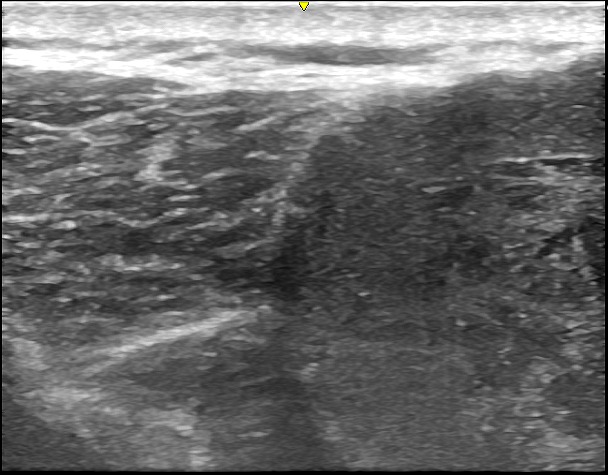

徐々に皮下腫瘍が大きくなったため、当院を受診されました。左肩に120mm大の巨大な皮下腫瘍があり、超音波検査の結果、典型的な粉瘤と診断されました。

術前